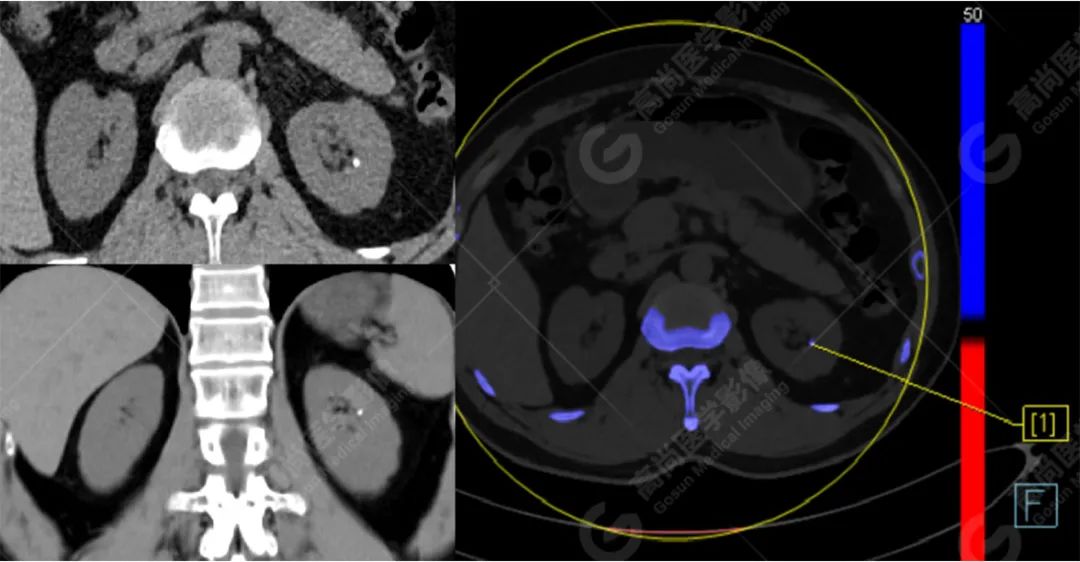

病例二

病史摘要:

患者左肾小结石,双能量 CT 结石分析示其主要成分为草酸盐。

CT 平扫因其安全性和高度敏感性已成为评估泌尿系结石的标准检查方法。而双源 CT(dual-source computed tomography,DSCT)在一次扫描过程中能够同时进行低能量和高能量扫描,使其拥有能够对电子密度相同但光子吸收能力不同的结石进行鉴别的能力。

计算感兴趣区结石在低能量和高能量原位扫描下的衰减值比值(AR 值),与体外结石的已知化学成分的 AR 值进行对比,因此得到体内结石的化学成分。(此步骤在工作站进行,如上成分标识图)